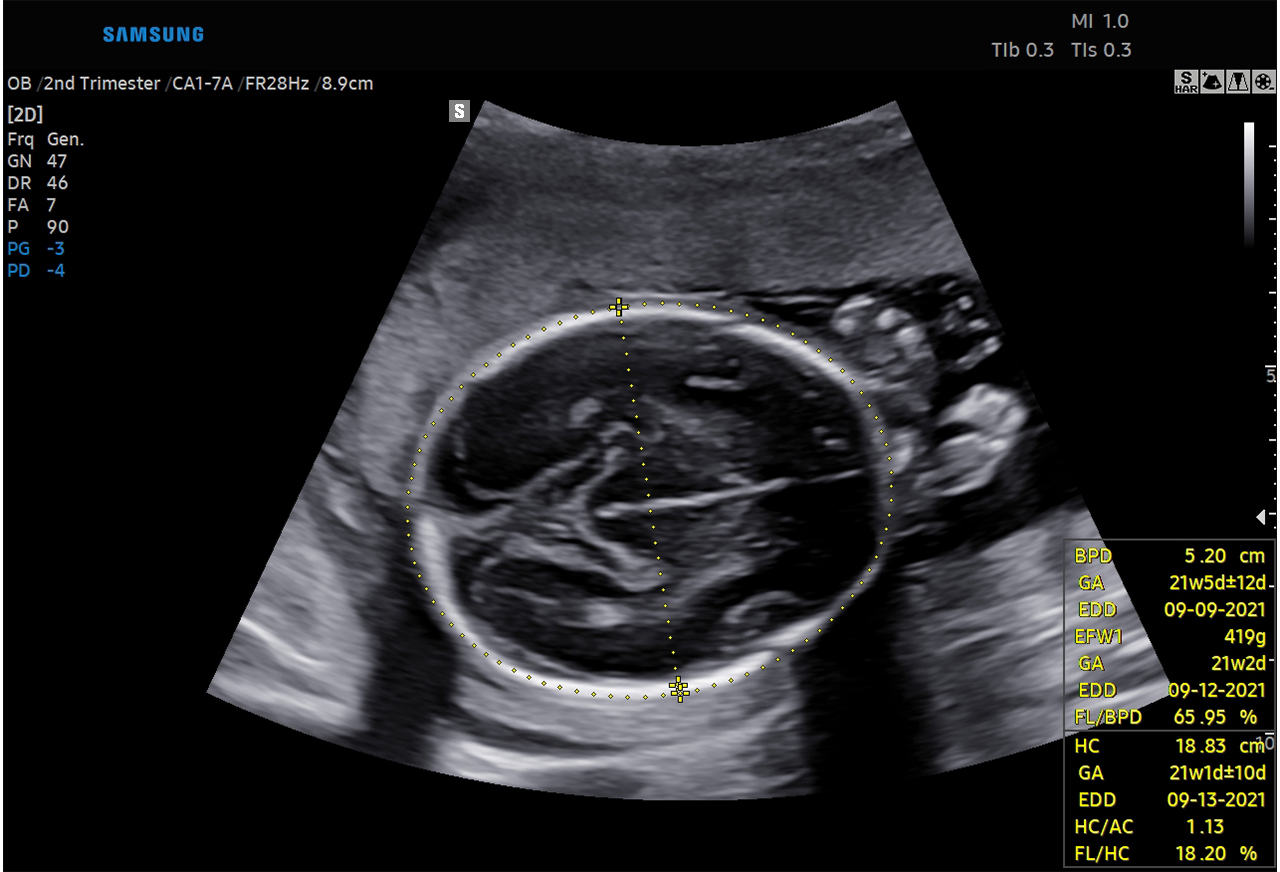

‘Biometry Solution’ recognizes images such as the fetal head, abdomen, lower extremities and others and measures the fetal growth and development while the ‘Fetal Heart Solution’ recognizes the view of the fetal heart, annotates the images and measures the necessary fetal heart structures for a thorough fetal heart anomaly assessments.

The image delineates that the fetal head is automatically recognized and measured along with the fetal growth when ‘Biometry Solution’ is executed.